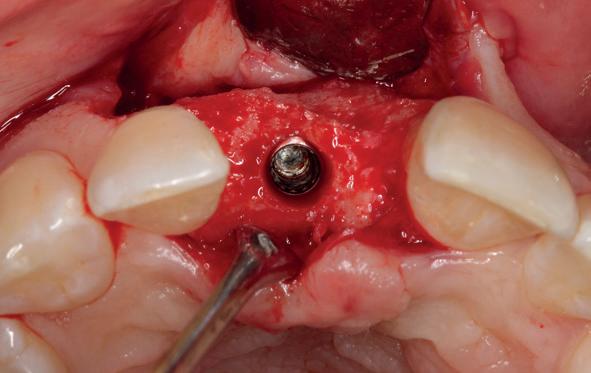

5. Implantaten geplaatst op geleide van een boorsjabloon; botopbouw met sinuslift volgens de GBR-techniek en Caldwell Luc methode; materialen: Oragraft & BioOss, Ossix membr, hyaluronzuur. In de BK is gekozen voor Bego implantaten (Bego SC en RSX 3,75x 11,5 & 13mm).

6. In het front zijn Bego 3,25mm

Tijdens de chirurgische behandeling worden na het afschuiven van de flap de posities bepaald van de implantaten met de boorsjabloon. In de bovenkaak worden 7 implantaten geplaatst en in de onderkaak 8

implantaten geplaatst terwijl in de zijdelingse delen voor een bredere diameter (3,75 & 4,1) is gekozen, met lengte 8,5 en 10mm.

(zie foto’s chirurgie en OPT’s). Gekozen is voor Bego SC & RSX Pro van een relatief smalle diameter (3,253,75). Alleen in de molaarstreek valt de keuze op een 4,1 mm in diameter. De lengte varieert tussen 8,5 en 13 mm afhankelijk van de ligging van de nervus alveolaris inferior en het foramen mentale als de neusbodem en de sinusholte. De keuze van de diameter wordt mede bepaald door de breedte van de processus ondanks de uit te voeren laterale botopbouw. Indien mogelijk gaat de voorkeur uit naar het plaatsen van implantaten in autoloog en daarmee vitaal bot.